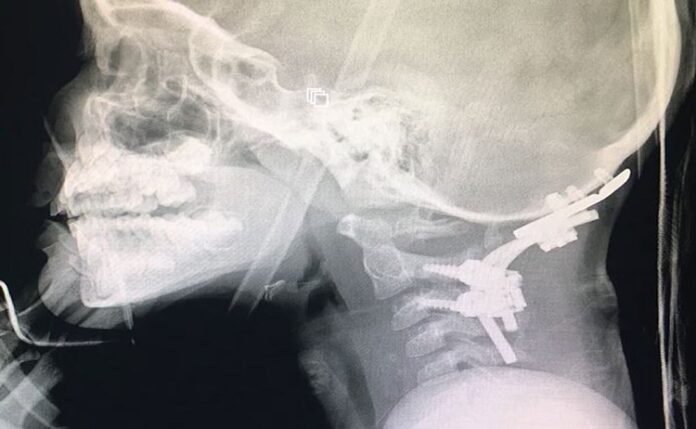

El palestino Suleiman Hassan, de doce años, de Cisjordania, sufrió una decapitación interna , donde la base del cráneo y la parte superior de la columna se desprendieron, pero la piel aún está intacta.

La decapitación interna es una lesión extremadamente rara que ocurre cuando un impacto repentino hace que los ligamentos y los músculos que sujetan la cabeza a las vértebras superiores de la columna se desgarren.

Los médicos dijeron que la cabeza del niño se había «desprendido casi por completo de la base del cuello», pero la piel y los principales vasos sanguíneos permanecieron intactos.

“El procedimiento en sí es muy complicado y tomó varias horas. Mientras estaba en la sala de operaciones, usamos placas y fijaciones nuevas en el área dañada.

La lesión se trata fusionando el cráneo y la columna vertebral usando varillas, tornillos, placas y posiblemente injertos óseos.